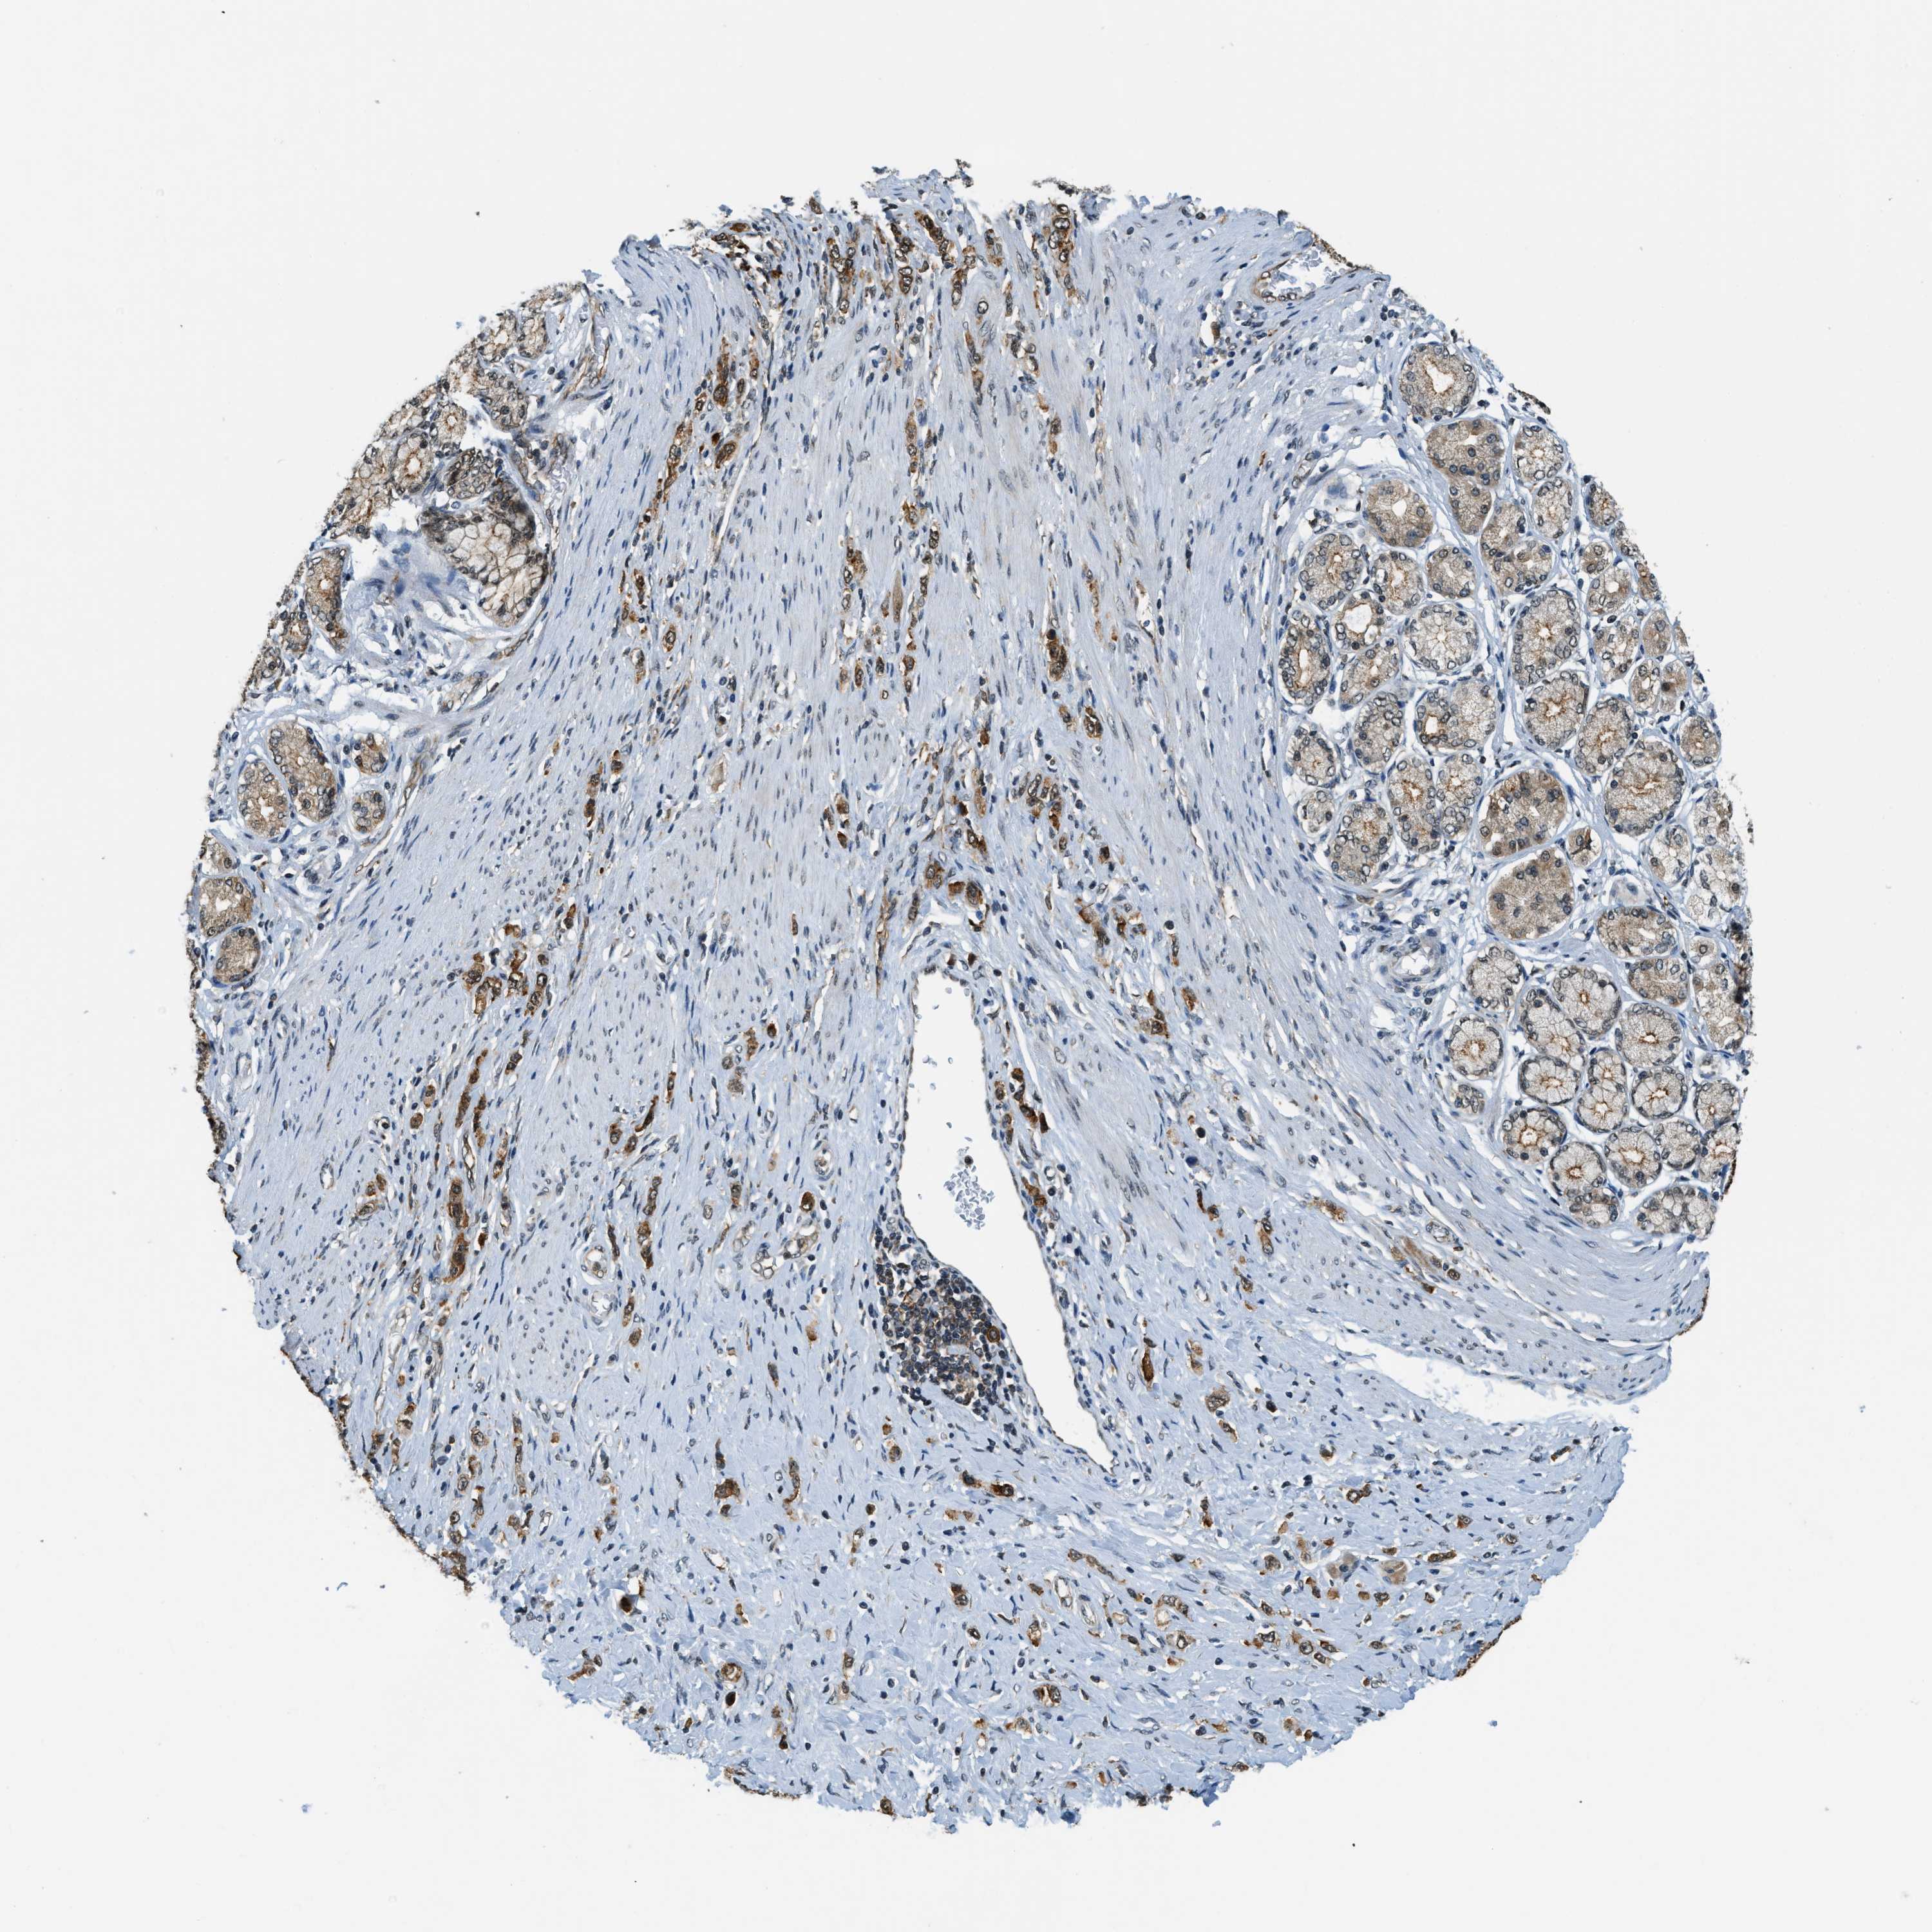

STOMACH CANCER - Protein expressioni

A mouse-over function shows sample information and annotation data. Click on an image to view it in a full screen mode. Samples can be filtered based on level of antibody staining by selecting one or several of the following categories: high, medium, low and not detected. The assay and annotation is described here.

Note that samples used for immunohistochemistry by the Human Protein Atlas do not correspond to samples in the TCGA dataset.

Antibody stainingi

Antibody staining in the annotated cell types in the current human tissue is reported as not detected, low, medium, or high, based on conventional immunohistochemistry profiling in selected tissues. This score is based on the combination of the staining intensity and fraction of stained cells.

Each image is clickable and will lead to virtual microscopy that enables deeper exploration of all samples and also displays staining intensity scores, fraction scores and subcellular localization as well as patient and tissue information for each sample.

Antibody HPA023904

Antibody HPA024010

Antibody HPA025960

Antibody CAB017037

Staining

High

Medium

Low

Not detected

Intensity

Strong

Moderate

Weak

Negative

Quantity

>75%

75%-25%

<25%

None

Location

Nuclear

Cytoplasmic/membranous

Cytoplasmic/membranous,nuclear

Adenocarcinoma, NOS